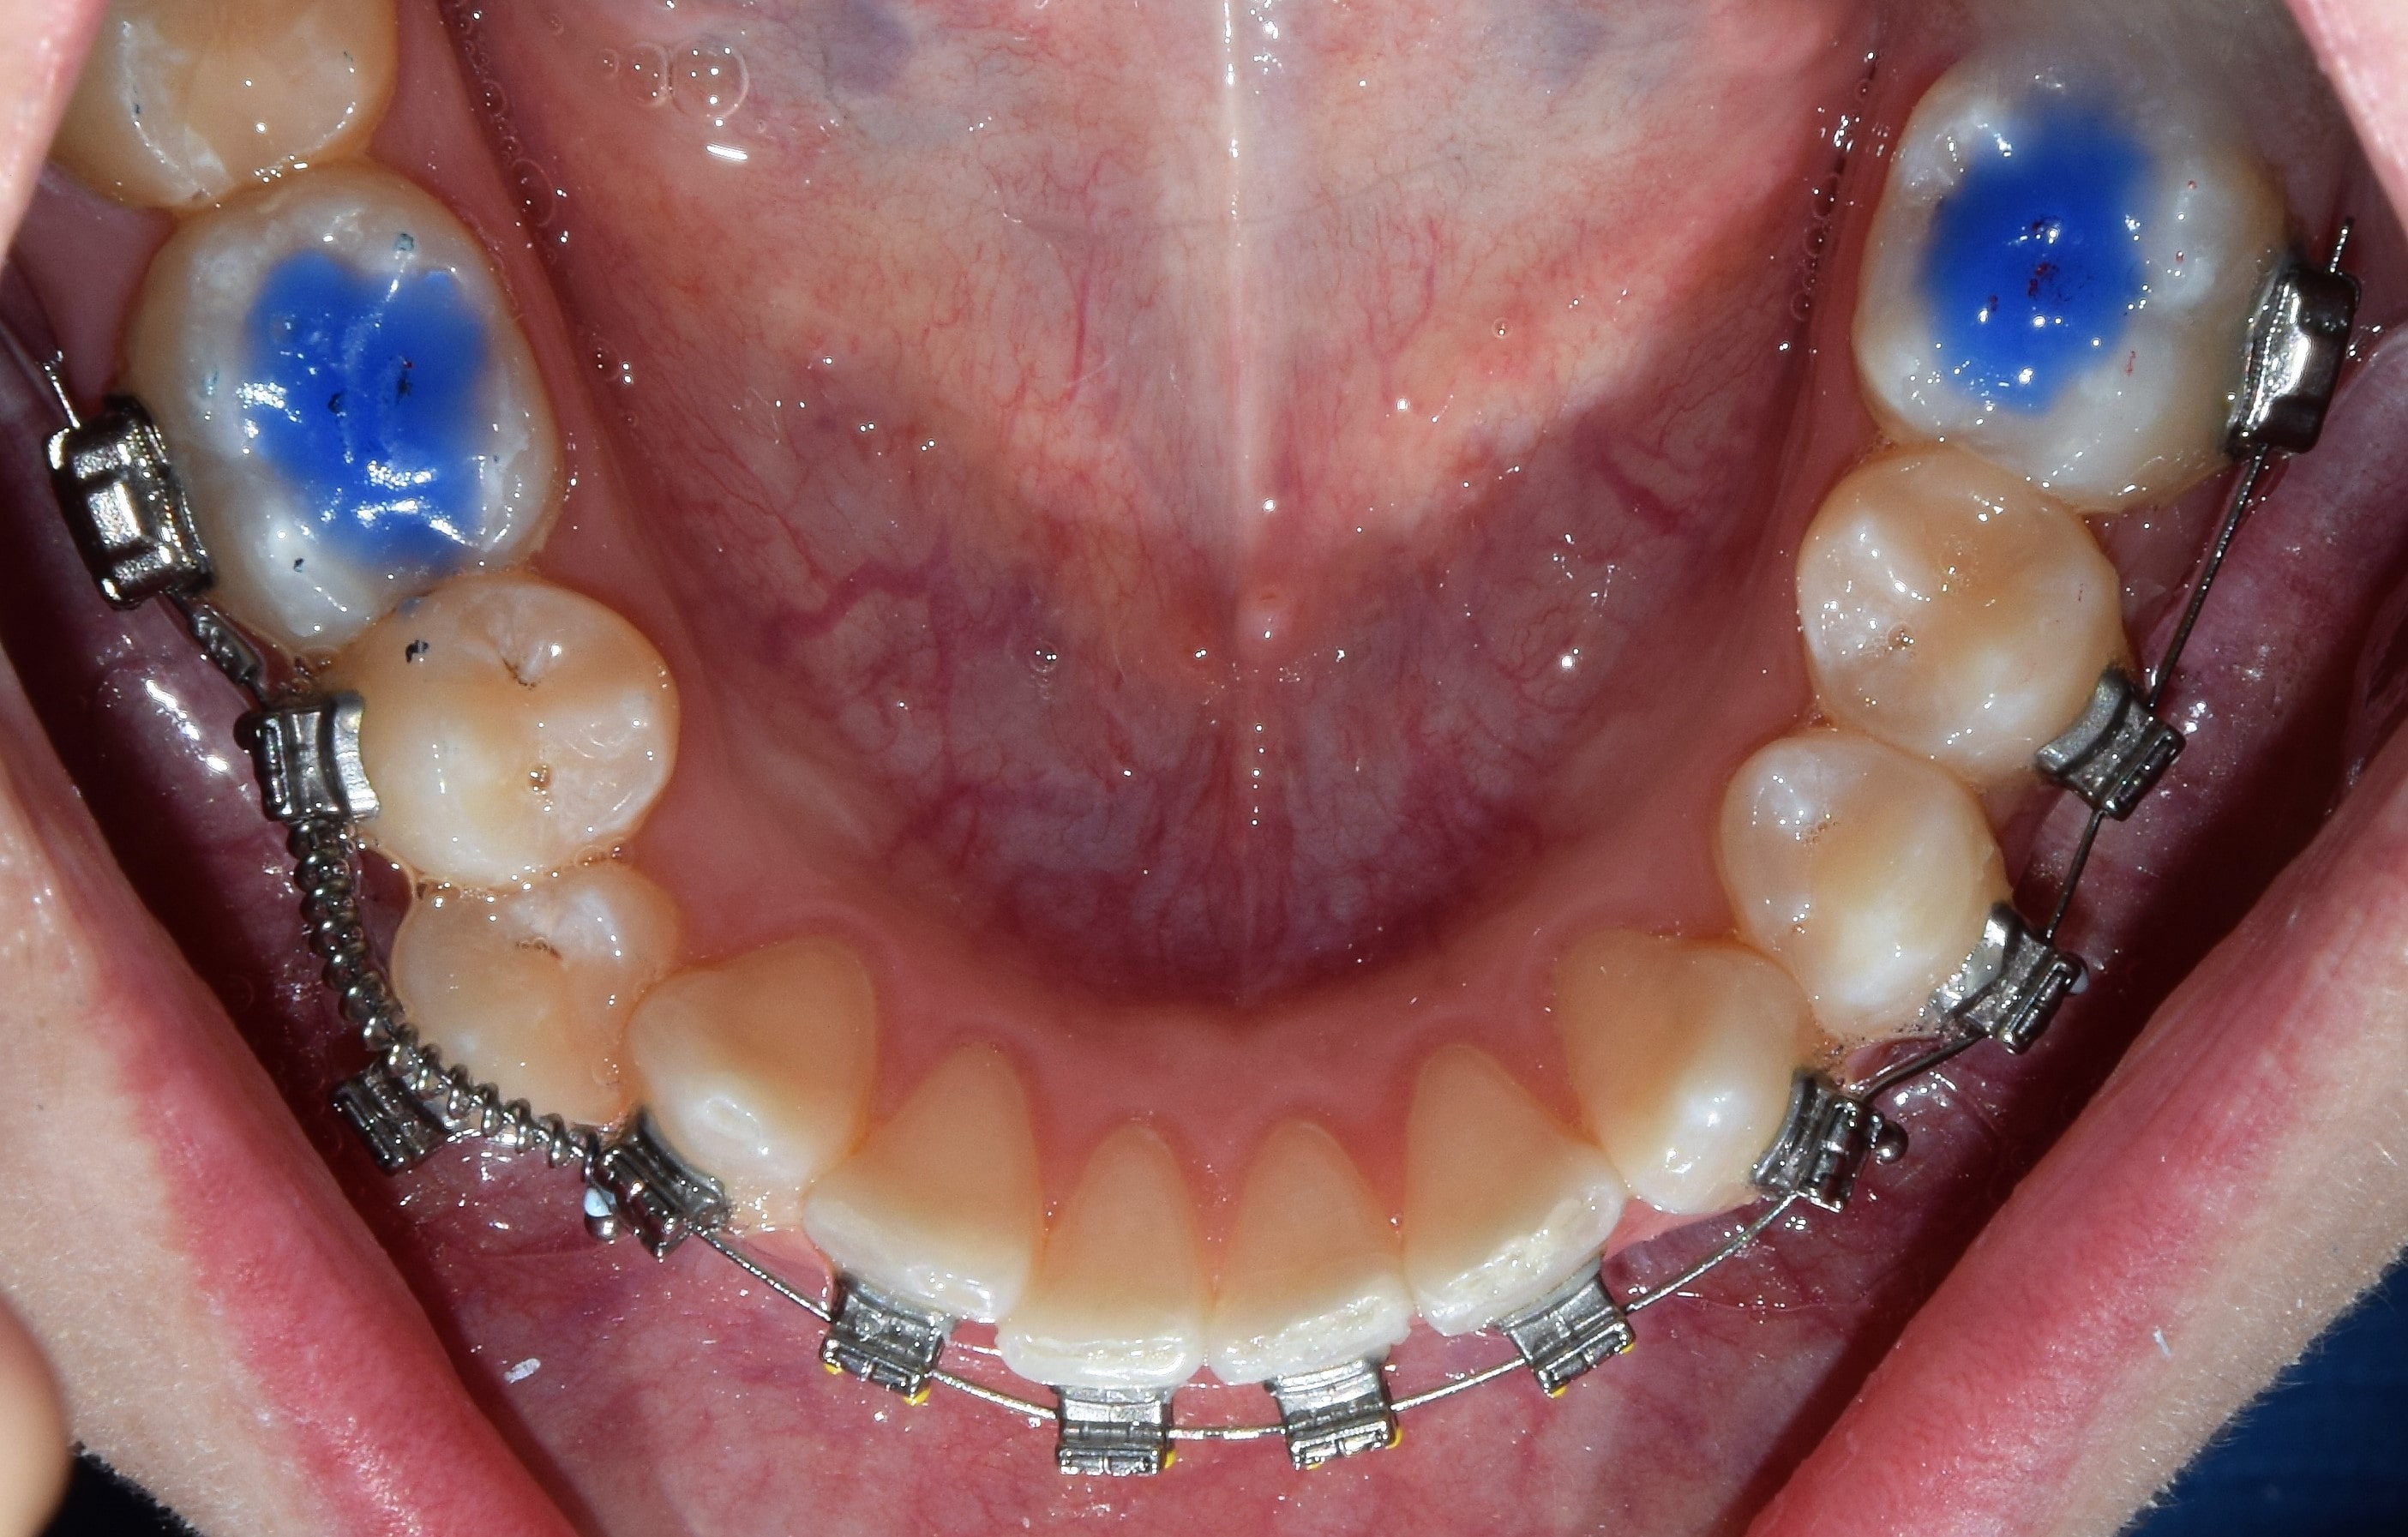

Harapásemelő

Harapásemelők alatt a fogak rágó (oldalsó fogaknál), vagy belső (elülső fogaknál) felszínre ragasztott, színes tömőanyagból készült blokkokat értjük. Ezeknek köszönhetően eltávolodik egymástól az alsó felső fogív, és mivel a fogak nem érintkeznek egymással, gyorsabb és fájdalommentesebb a fogmozgatás. További nagy előnyük, hogy mivel az alsó-felső fogív a kezelés elején csak a harapásemelőkön érintkezik egymással, így a bracketekre nem lehet ráharapni, azok nem esnek le. Segítségünkre vannak mind a nyitott-, mind a mélyharapás kezelésében. Minden kezelésemnél használok harapásemelőt. Eltávolításuk speciális fúrókkal történik, így a fogzománcot nem sértjük meg.